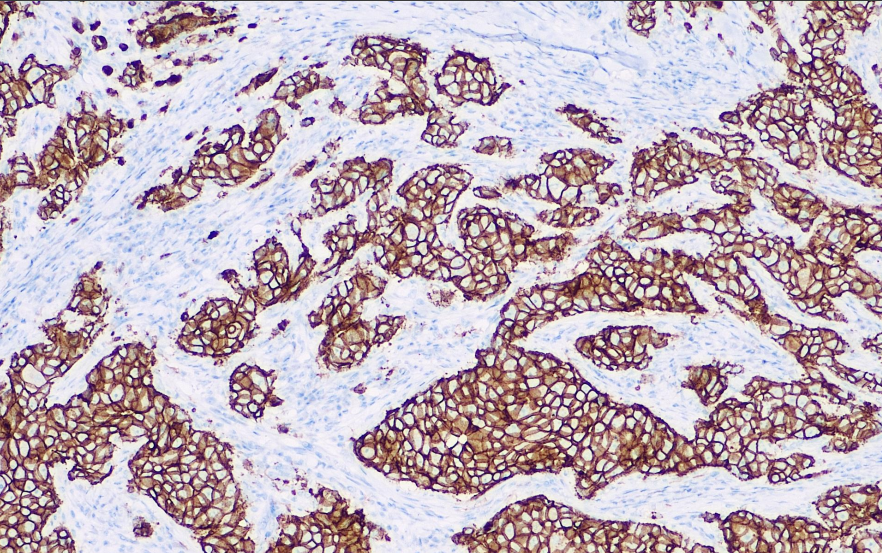

阳性对照: 乳腺癌

E-Cadherin是一种在上皮细胞中表达的粘附蛋白。在腺上皮以及肺、胃肠道腺癌和卵巢中存在表达。可用于区分腺癌(+)和间皮瘤(-),乳腺导管癌(+)和乳腺小叶癌(-),在一些甲状腺癌中呈阳性。E-Cadherin在乳腺癌和非小细胞肺癌中的表达下降或缺失,常作为预后不良的标志。目前主要用于各种恶性肿瘤细胞的侵袭和转移的研究,是肿瘤进展、预后的重要标记物之一。

E-Cadherin抗体试剂可与E-Cadherin分子抗原特异性结合,含E-Cadherin抗体试剂的免疫组化试剂盒适用于乳腺癌和胃癌的精准诊断。